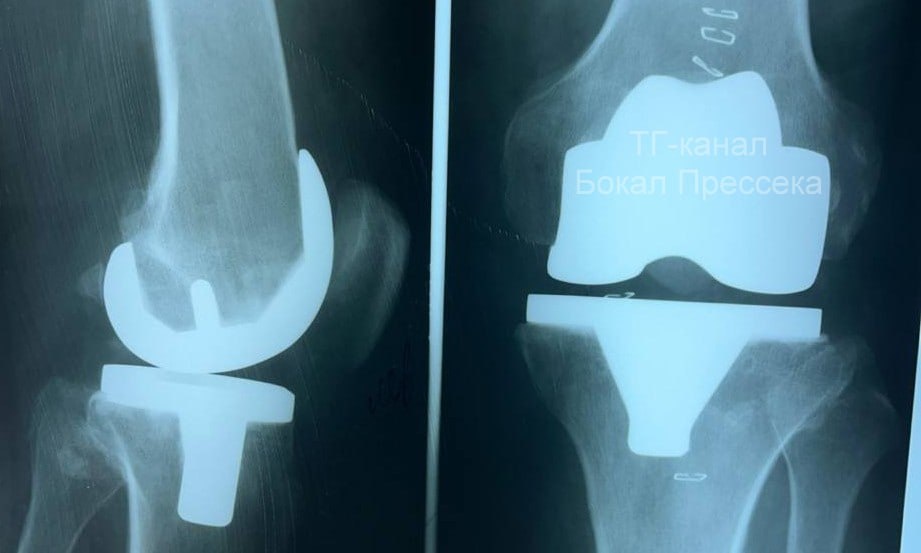

Эндопротезирование коленного сустава впервые провели в больнице № 13 Нижнего Новгорода. Об этом рассказал редактор «Стационар-пресс» Алексей Никонов в своем Telegram-канале.

Операцию провели 59-летнему мастеру спорта по боксу, который повредил колено. Эндопротезирование прошло успешно, и пациент уже самостоятельно передвигается на костылях.